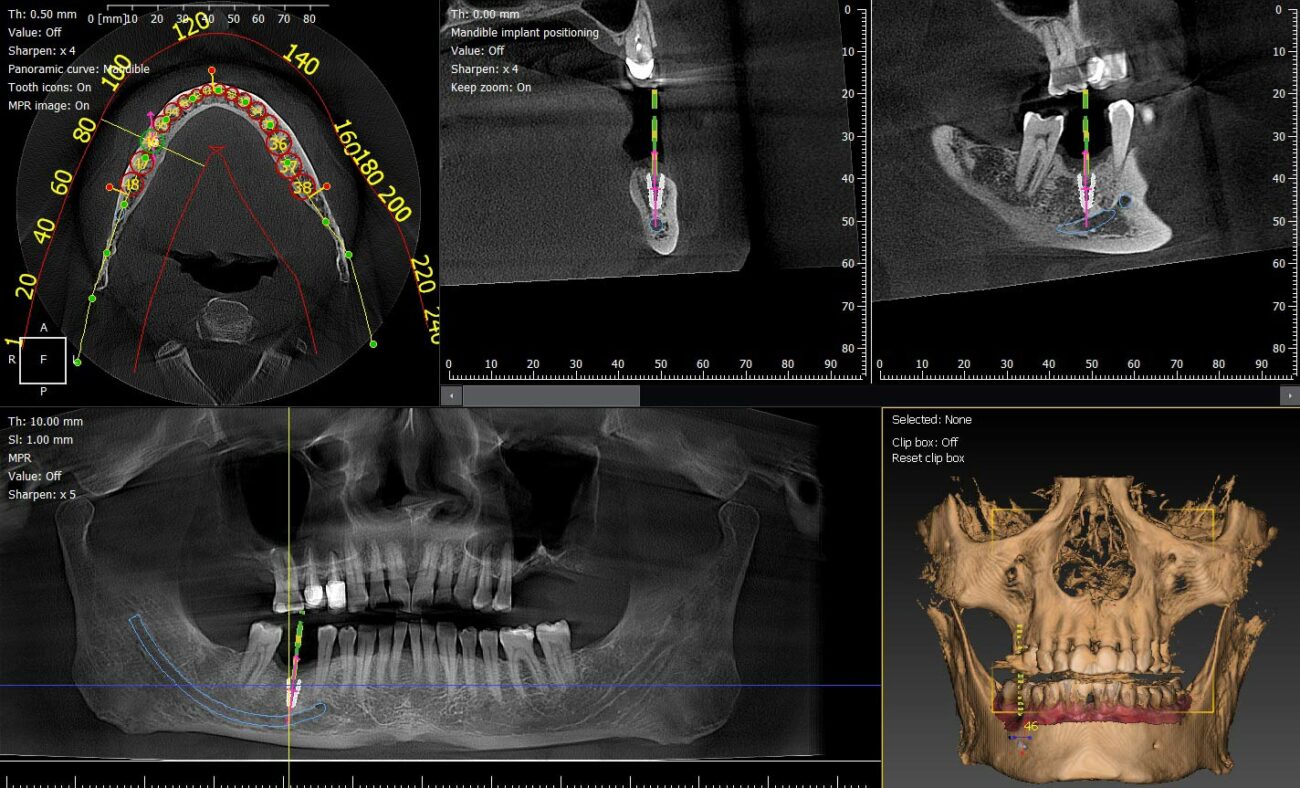

CBCT dentaire de nouvelle génération avec intelligence artificielle pour un diagnostic 3D de haute précision

CBCT dentaire: l’IA révolutionne la qualité du diagnostic 3D

L’imagerie dentaire connaît une évolution majeure. Grâce à l’intégration de l’intelligence...